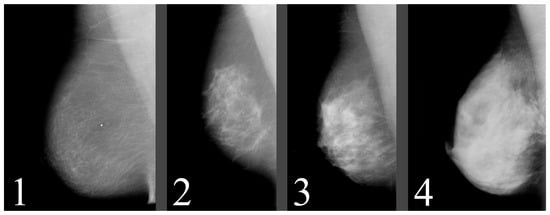

One disadvantage of the dataset is the low resolution of the images, which is only 1024 × 1024 pixels. This low resolution may potentially result in a loss of important information about microcalcifications. Moreover, many mammograms in the dataset may contain breast positional mistakes [20] and artifacts [21] (as shown in Figure 14). Additionally, the breast density assessment in the dataset does not meet the standards of the ACR BI-RADS Atlas. Since the images were acquired using the digitalization of the SFM method, they may contain unnecessary elements (as shown in Figure 15). These elements could have a negative impact during neural network training, and therefore, their removal should be considered.

Figure 14. Artifacts pointed to by arrows, left and middle images without pectoral muscle, and middle and right images do not contain whole breasts. Source: [19].